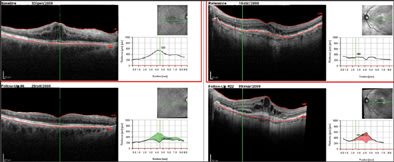

In both cases, atrophy of the retina, as identified on OCT, explains the better visualization of subretinal structures. In particular, choroidal vessels are evident and their limits are sharper than under normal retina areas; even sclera could be visualized under choroidal vessels. Note that, along the scan line, there is an area of hypertrophic RPE area corresponding in retinal imaging to 1 of the residual autofluorescent zones surrounded by atrophy. In Figure 4, a comparison is shown between SD-OCT (top panel) and TD-OCT (bottom panel) images of the right eye. Best-corrected VA in this eye was 20/32 because of a relatively conserved neuroretina in the foveal region. The retina is diffusely thinned so that choroid and choriocapillaris are visible. Note the high backscattering (*) in correspondence of an atrophy area: In SD-OCT imaging, choroidal vessels are more distinguishable than in TD-OCT images.

Figure 4. Dry AMD analyzed with SD-OCT (top panel) and TD-OCT (bottom panel). General thinning of retina explains the good visualization of choroid. Note the area of atrophy with high backscattering (*). Analysis of RPE condition in this area is only possible using SD-OCT, while TD-OCT does not permit distinguishing this layer from the choriocapillaris and choroid.

Moreover, the software allows the viewer to set a scan as a reference. In the following visits, the eye-tracking system will be able to perform the OCT scans in the exact position of the previous examination, recognizing some "key" points on the retinal surface and thus making the follow-up analysis more efficient (Figure 6).

Figure 6. Two follow-up samples: In the left panel, cystoid macula edema disappearing in following visits (the software shows a green area corresponding to the reduced thickness). In the right panel, two consequence examinations of a CNV lesion with increasing edema and developing of subretinal fluid (the red area represents the increased retinal thickness). The green arrow on the SLO image corresponds with the exact scan line.